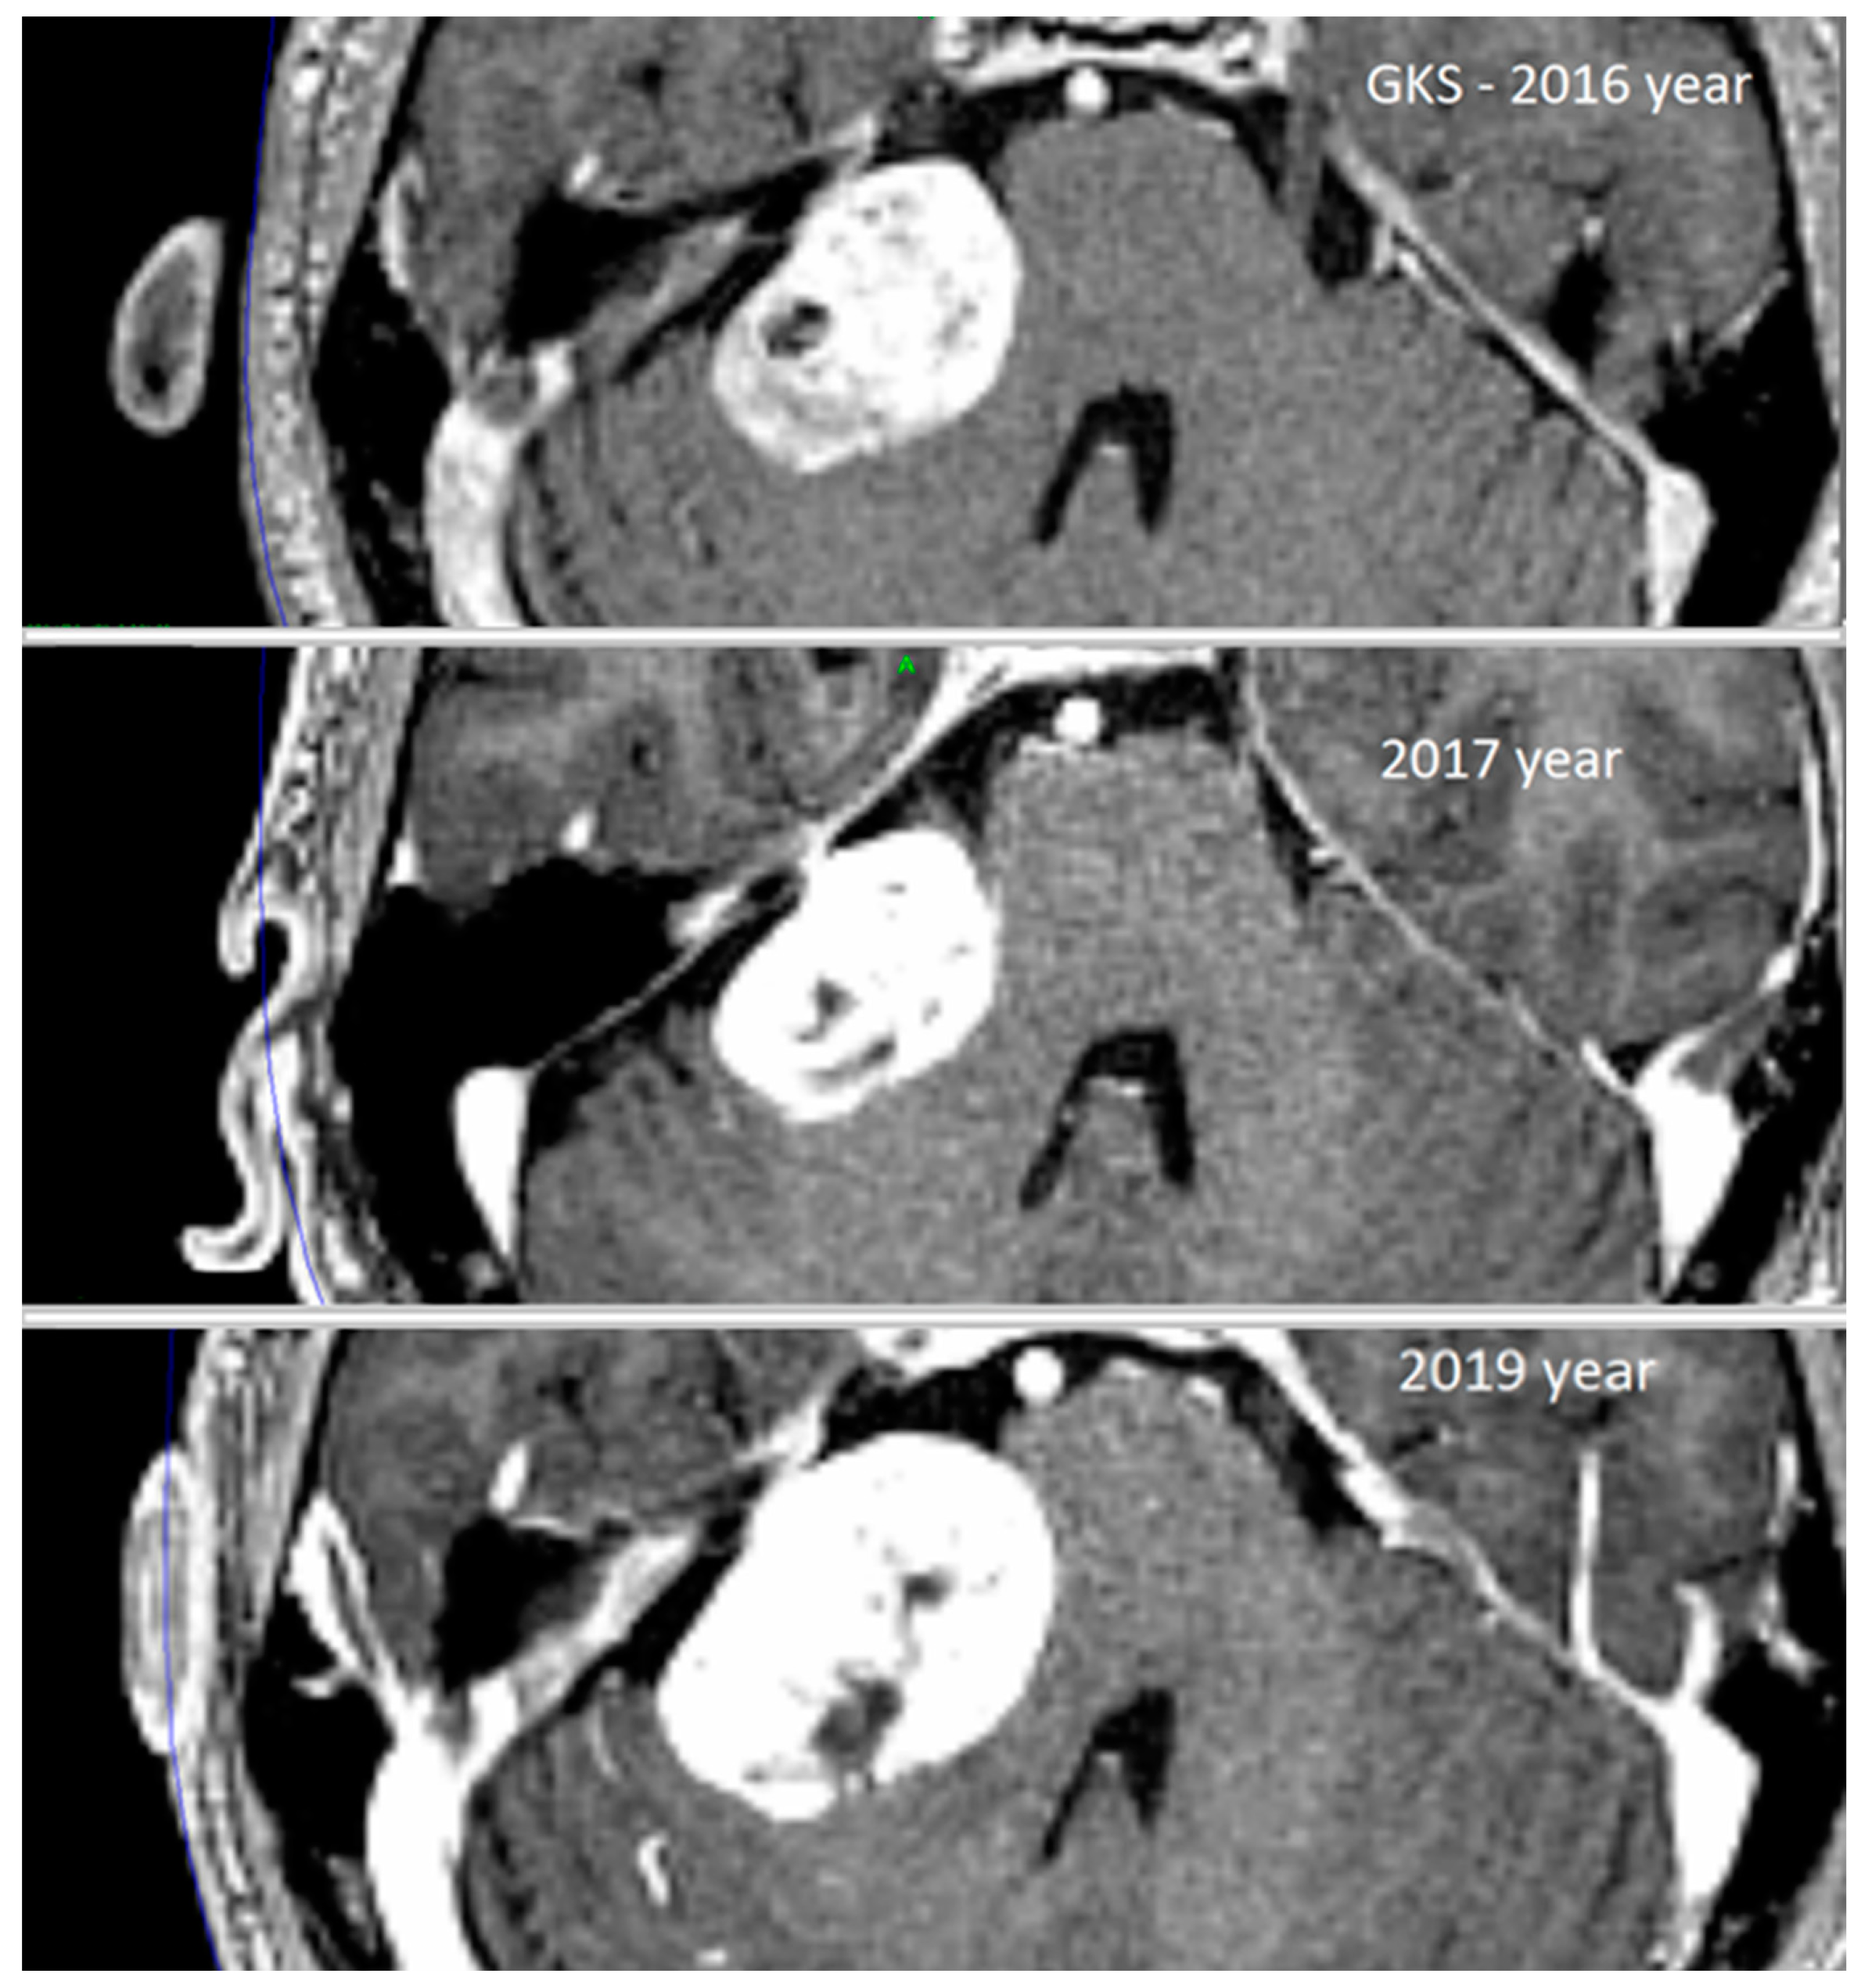

| 1. | 4 | 4 | 10.2 | 15.0 | 1.9 | 1.7 | 12 | 8.1 | + | solid | 32 | 42 |

| 2. | 3 | 4 | 3.2 | 4.4 | 1.2 | 0.4 | 12 | 6.8 | - | solid | 12 | 26 |

| 3. | 4 | 4 | 4.7 | 12.3 | 1.1 | 0.8 | 12 | 9.9 | - | necrosis | 24 | 36 |

| 4. | 4 | 4 | 4.5 | 8.3 | 0.3 | 0.03 | 12 | 5.6 | + | cystic | 24 | 84 |

| 5. | 4 | 4 | 7.7 | 9.4 | 2.2 | 1.9 | 12 | 7.6 | - | necrosis | 24 | 36 |

| 6. | 4 | 4 | 8.2 | 11.7 | 1.6 | 1.2 | 12 | 8.5 | + | necrosis | 24 | 38 |

| 7. | 3 | 4 | 3.9 | 7.7 | 1.2 | 0.5 | 12 | 6.2 | - | solid | 18 | 52 |

| 8. | 4 | 4 | 5.0 | 10.3 | 2.1 | 1.1 | 12 | 7.5 | - | necrosis | 27 | 46 |

| Mean: | 3.75 | 4 | 5.9 ± 2.5 | 9.9 ± 3.2 | 1.5 ± 0.6 | 0.9 ± 0.6 | 12 | 7.5 ± 1.4 | - | - | 22 ± 5.9 | 45 ± 17.5 |